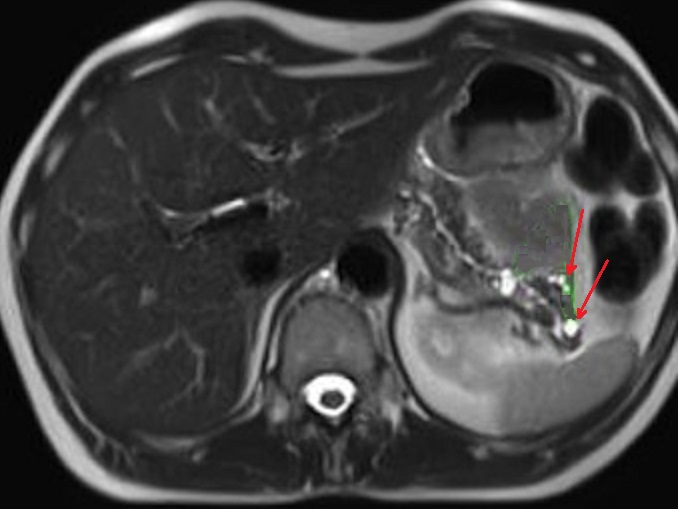

Sus les coupes IRM pondere

sur T2 Image radiolofique des TIPMP de type canaux

secondaire sont des kystes unique ou multiple

arondie ou ovalaire polylobulaire de fortement

hyperintense et comunication souvent avec canal

principale CPP ( fleche rouge ) . Image radiologique

IRM ponderation sur T2 , en coupe axiale |